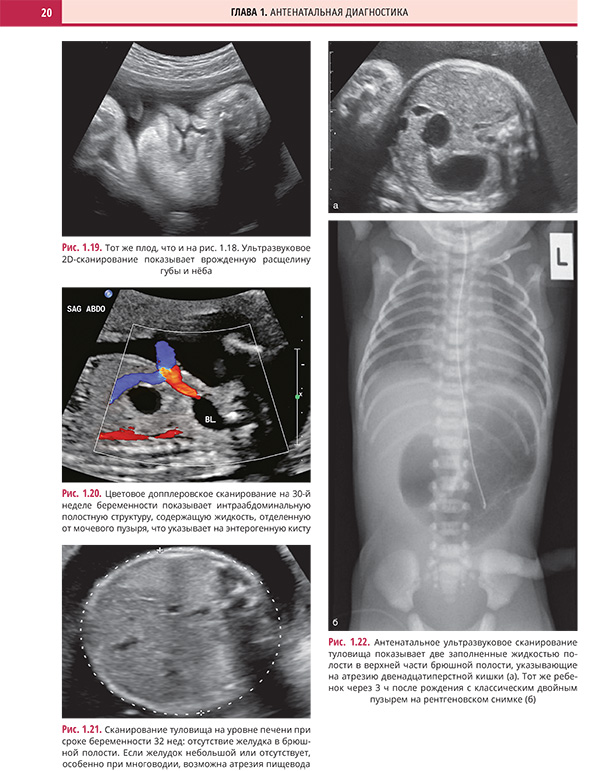

Глава 1. Антенатальная диагностика